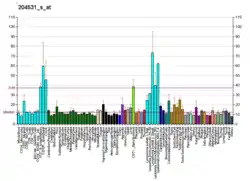

Low expression of BRCA1 in breast and ovarian cancers

BRCA1 expression is reduced or undetectable in the majority of high grade, ductal breast cancers.[63] It has long been noted that loss of BRCA1 activity, either by germ-line mutations or by down-regulation of gene expression, leads to tumor formation in specific target tissues. In particular, decreased BRCA1 expression contributes to both sporadic and inherited breast tumor progression.[64] Reduced expression of BRCA1 is tumorigenic because it plays an important role in the repair of DNA damages, especially double-strand breaks, by the potentially error-free pathway of homologous recombination.[65] Since cells that lack the BRCA1 protein tend to repair DNA damages by alternative more error-prone mechanisms, the reduction or silencing of this protein generates mutations and gross chromosomal rearrangements that can lead to progression to breast cancer.[65]

Similarly, BRCA1 expression is low in the majority (55%) of sporadic epithelial ovarian cancers (EOCs) where EOCs are the most common type of ovarian cancer, representing approximately 90% of ovarian cancers.[66] In serous ovarian carcinomas, a sub-category constituting about 2/3 of EOCs, low BRCA1 expression occurs in more than 50% of cases.[67] Bowtell[68] reviewed the literature indicating that deficient homologous recombination repair caused by BRCA1 deficiency is tumorigenic. In particular this deficiency initiates a cascade of molecular events that sculpt the evolution of high-grade serous ovarian cancer and dictate its response to therapy. Especially noted was that BRCA1 deficiency could be the cause of tumorigenesis whether due to BRCA1 mutation or any other event that causes a deficiency of BRCA1 expression.

MicroRNA repression of BRCA1 in breast cancers

There are a number of specific microRNAs, when overexpressed, that directly reduce expression of specific DNA repair proteins (see MicroRNA section DNA repair and cancer) In the case of breast cancer, microRNA-182 (miR-182) specifically targets BRCA1.[73] Breast cancers can be classified based on receptor status or histology, with triple-negative breast cancer (15%–25% of breast cancers), HER2+ (15%–30% of breast cancers), ER+/PR+ (about 70% of breast cancers), and Invasive lobular carcinoma (about 5%–10% of invasive breast cancer). All four types of breast cancer were found to have an average of about 100-fold increase in miR-182, compared to normal breast tissue.[74] In breast cancer cell lines, there is an inverse correlation of BRCA1 protein levels with miR-182 expression.[73] Thus it appears that much of the reduction or absence of BRCA1 in high grade ductal breast cancers may be due to over-expressed miR-182.

In addition to miR-182, a pair of almost identical microRNAs, miR-146a and miR-146b-5p, also repress BRCA1 expression. These two microRNAs are over-expressed in triple-negative tumors and their over-expression results in BRCA1 inactivation.[75] Thus, miR-146a and/or miR-146b-5p may also contribute to reduced expression of BRCA1 in these triple-negative breast cancers.

MicroRNA repression of BRCA1 in ovarian cancers

In both serous tubal intraepithelial carcinoma (the precursor lesion to high grade serous ovarian carcinoma (HG-SOC)), and in HG-SOC itself, miR-182 is overexpressed in about 70% of cases.[76] In cells with over-expressed miR-182, BRCA1 remained low, even after exposure to ionizing radiation (which normally raises BRCA1 expression).[76] Thus much of the reduced or absent BRCA1 in HG-SOC may be due to over-expressed miR-182.

Another microRNA known to reduce expression of BRCA1 in ovarian cancer cells is miR-9.[66] Among 58 tumors from patients with stage IIIC or stage IV serous ovarian cancers (HG-SOG), an inverse correlation was found between expressions of miR-9 and BRCA1,[66] so that increased miR-9 may also contribute to reduced expression of BRCA1 in these ovarian cancers.